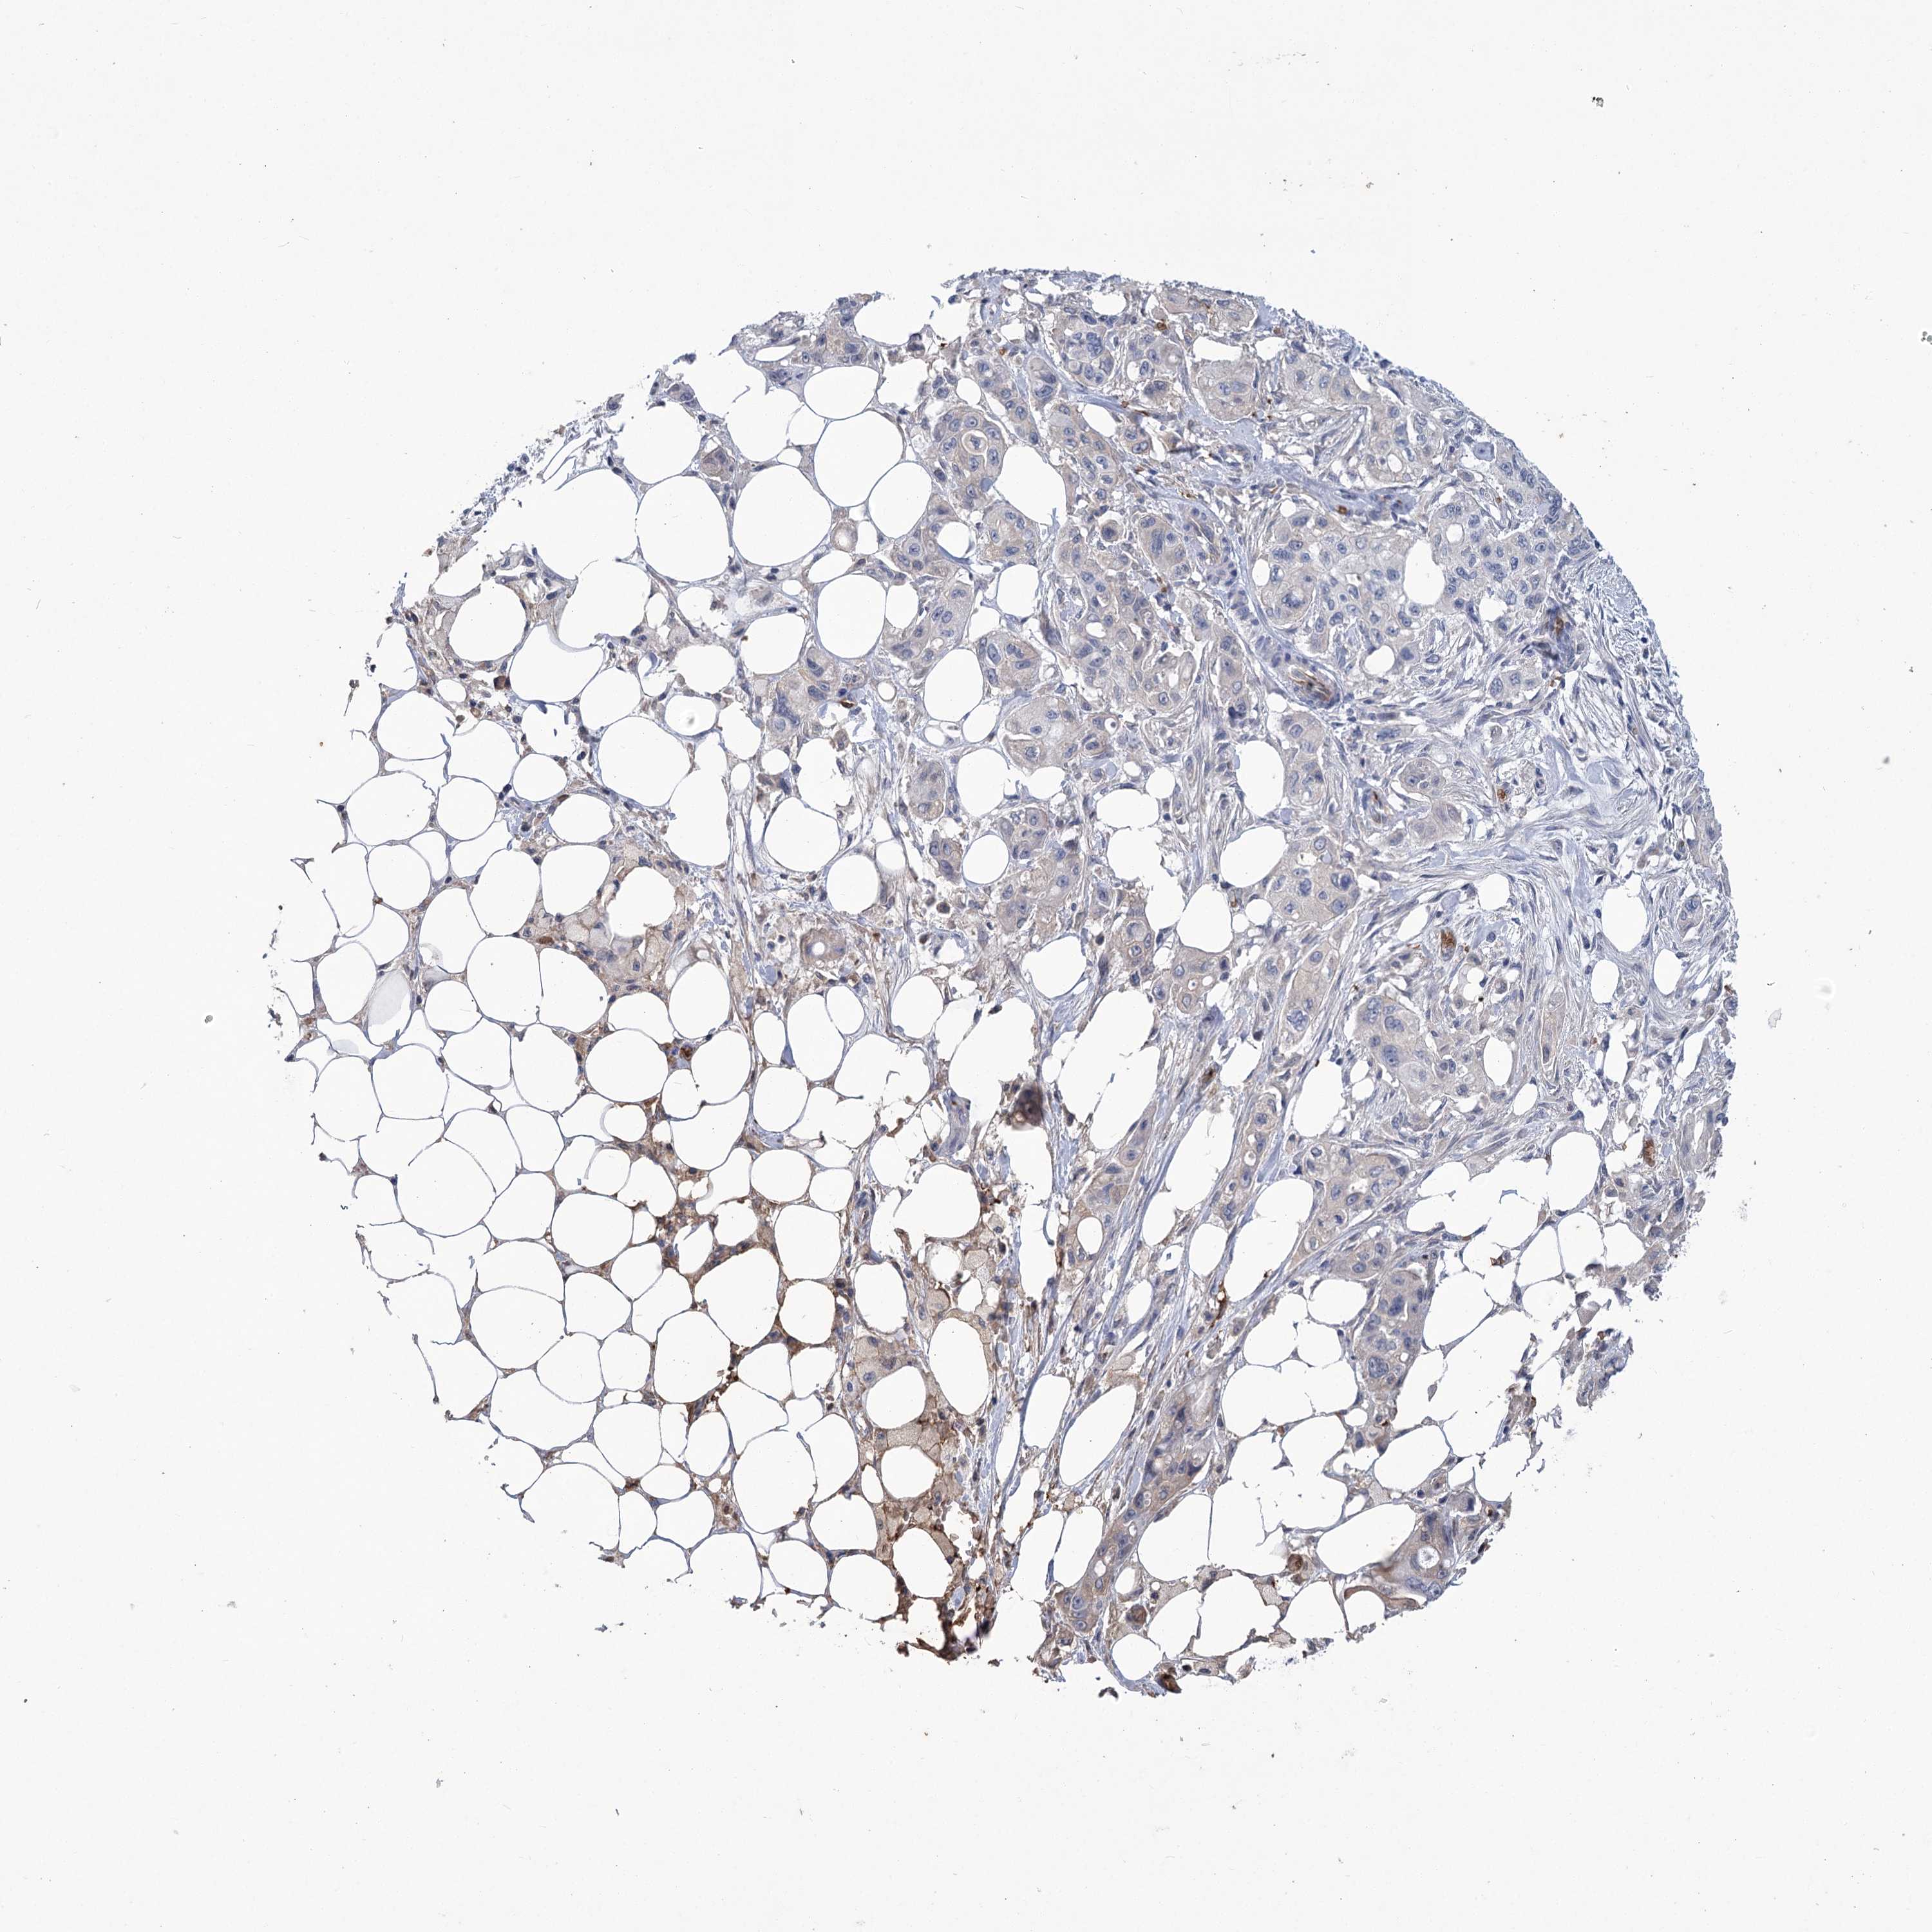

PANCREATIC CANCER - Protein expressioni

A mouse-over function shows sample information and annotation data. Click on an image to view it in a full screen mode. Samples can be filtered based on level of antibody staining by selecting one or several of the following categories: high, medium, low and not detected. The assay and annotation is described here.

Note that samples used for immunohistochemistry by the Human Protein Atlas do not correspond to samples in the TCGA dataset.

Antibody stainingi

Antibody staining in the annotated cell types in the current human tissue is reported as not detected, low, medium, or high, based on conventional immunohistochemistry profiling in selected tissues. This score is based on the combination of the staining intensity and fraction of stained cells.

Each image is clickable and will lead to virtual microscopy that enables deeper exploration of all samples and also displays staining intensity scores, fraction scores and subcellular localization as well as patient and tissue information for each sample.

Antibody HPA043780

Antibody CAB032534

Adenocarcinoma, NOS